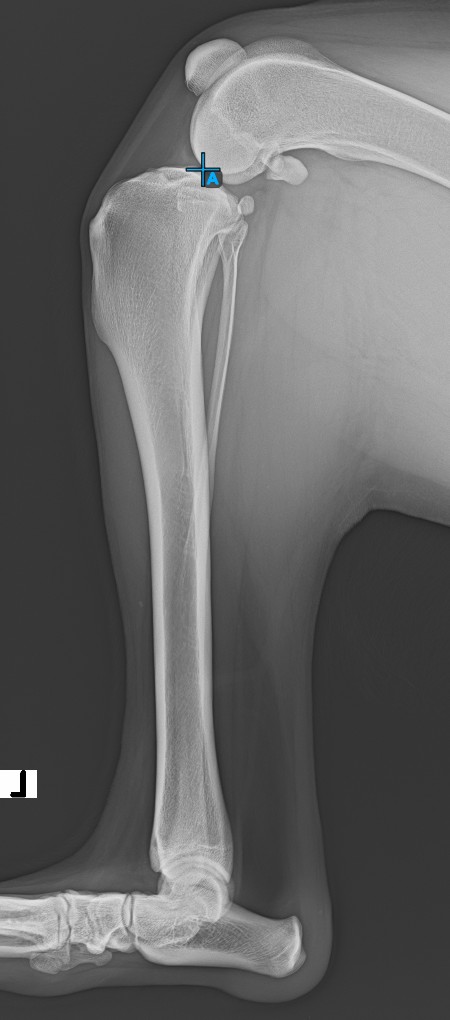

Start the measurement by marking the Eminentia Intercondylaris, which is located on the joint connecting the femur and the tibia.

The image below depicts the usual placement of the Eminentia Intercondylaris point.

Continue by marking the midpoint of the Cochlea, located at the end of the tibial bone. The line created between the Eminentia Intercondylaris and the midpoint of the Cochlea represents the long axis of the tibia.

The image below depicts the usual placement of the midpoint of the Cochlea.